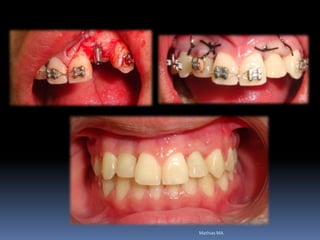

•Necessidades de reabilitações prévias

Dentística, periodontia, cirurgia, prótese, endodontia , ortodontia e DTMs

Reabilitação por implantes abre a visão de um

planejamento prévio, melhorando as condições da

área de trabalho antes da fixação por implantes

•Dentística/prótese

•Endodontia/periodontia

•Cirurgia/ortodontia